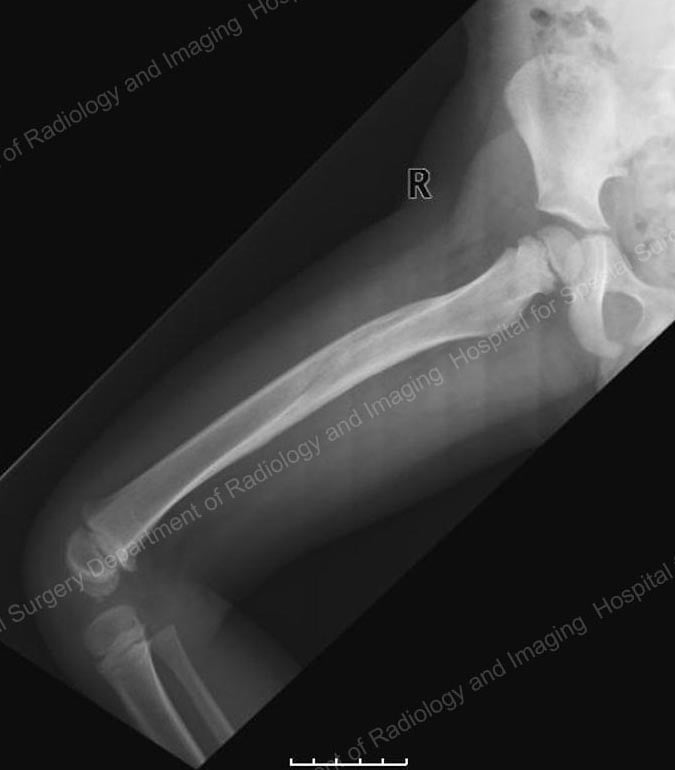

Since the early 2000s, many pediatric orthopedists have started using intramedullary nails or rods made from strong, lightweight, and flexible titanium to stabilize femur fractures in children aged five and older. In a relatively simple technique, the orthopedic surgeon makes two small incisions − about one inch in length − on either side of the knee. After the bone is realigned, the nails are inserted up through the center of the bone where they act as an internal splint during healing.

X-ray showing flexible intramedullary nails in place.

Intramedullary nails come in a range of diameters to accommodate the varying size of children’s bones. Generally no casting is necessary, however a knee immobilizer is commonly used for a few weeks to prevent movement and to keep the child comfortable. In most cases, a recovery period of three to six weeks of early healing is necessary before the child can begin walking on the injured leg. When the bone is completely healed, usually around one year after the injury occurs, the child returns to the hospital to have the nails removed.

Intramedullary nails are usually very well-tolerated. They are particularly useful in five- to ten-year-old children who have a thick lining around the bone called the periosteum, which might be likened to the peel on a banana. The periosteum helps keep the bone more stable and reduces the need for a heavy and rigid device, such as those that might be used in adults.